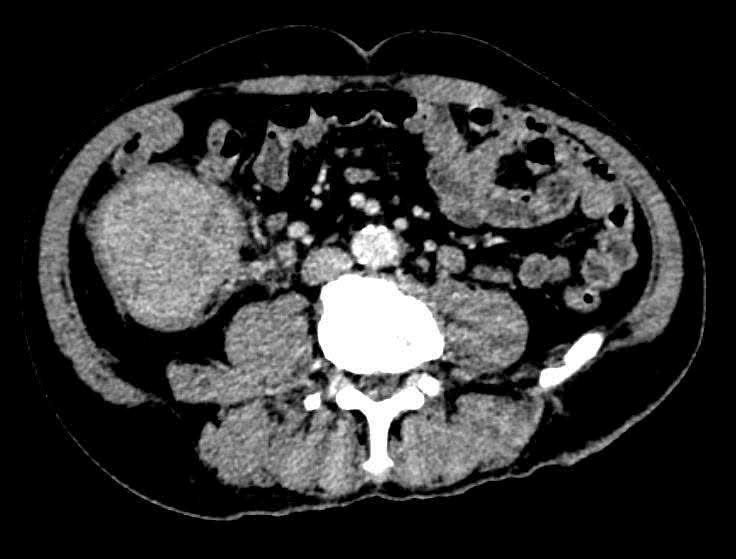

| Hình chụp của người bệnh khi khám sức khỏe tại bệnh viện. (Ảnh: BV198) |

Nội soi tiêu hóa phát hiện tổn thương nghi ngờ ác tính. Các thăm dò hình ảnh tiếp theo ghi nhận tổn thương di căn gan, cho thấy bệnh đã ở giai đoạn tiến triển.